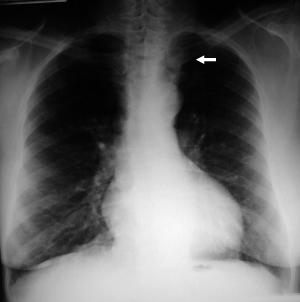

• Radiología del Tórax

Rx Torax Bocio Intratoracico

Rx. Tórax PA: aumento del diámetro transverso del mediastino superior por radiopacidad redondeada (flecha blanca) que comprime y desplaza la traquea hacia la derecha.